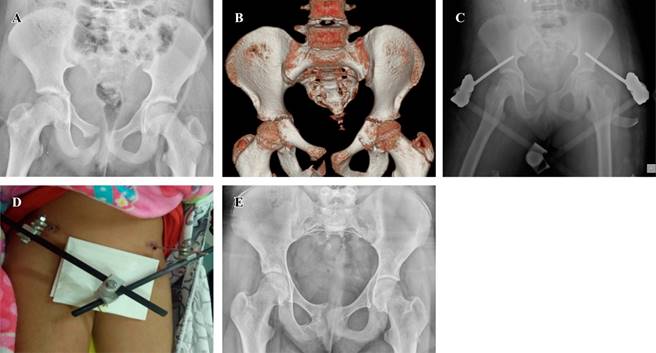

El tipo de fractura de pelvis más frecuente en los pacientes pediátricos tratados en nuestra unidad es el tipo III de Torode y Zieg, el cual, según el índice de Barthel, se asocia con el grado de independencia, los arcos de movilidad de cadera son completos y el tratamiento más frecuente para estas fracturas es conservador, por lo que el resultado clínico y funcional en estos pacientes es alto (Figuras 8 y 9).

Figura 9: Femenino de 10 años de edad con mecanismo de lesión de atropellamiento, Torode y Zieg IV, manejo quirúrgico con fijadores externos supraacetabulares, índice de Barthel (75 puntos) dependencia moderada, arcos de movilidad de cadera incompletos. A) Radiografía anteroposterior (AP) de pelvis inicial. B) Tomografía axial computarizada de pelvis inicial. C) Radiografía AP de pelvis al mes de evolución. D) Foto de la paciente al mes de evolución. E) Radiografía AP de pelvis a los cuatro meses de evolución.

Por lo tanto, el grado de severidad de la lesión no se relaciona con el resultado funcional o grado de independencia del paciente. Esto debido a que las características fisiológicas y biológicas de los niños permiten que la recuperación e independencia sea mejor que en los pacientes adultos.